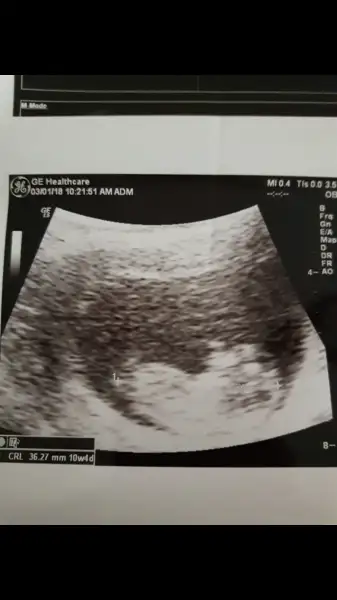

kızlar bidebenim bebegime bakın doktorum pazartesi günü erkeğe benzetmisti. Ama eminde olamayiz dedi sizde yorum yapin..

@GurbetGuzeli canım sende anliyosun bi bakarmısın

Işte burda

Eklentiler

• Screenshot_20171228-101645.webp

16,6 KB · Görüntüleme: 76

• Screenshot_20180103-121037.webp

9,2 KB · Görüntüleme: 66

Kiz gibi canim ama nerden anladin dersen erkek cocugunun vucudu daha netlesir erken zamanda ama tabi bu ultrasonun kalitesinde bagli daha kucuk tatlim bizimkiler ayniyizz bakalim ne cikcak bebisler